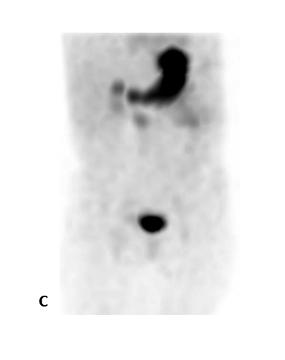

La scintigraphie au Pertechnétate de Tc99m est le test de choix pour identifier la muqueuse gastrique ectopique chez les patients dont la suspicion clinique est élevée. Cependant, quoique le diverticule puisse potentiellement être identifié sur la TDM faible dose si effectuée, s’il n’y pas de muqueuse gastrique ectopique ou cause de faux positif, l’étude scintigraphique par elle-même sera négative. Dans la scintigraphie au 99mTc-Pertechnétate, la captation du traceur est principalement au niveau des cellules sécrétrices de mucine mais son élimination est influencée par les cellules pariétales11,12. Sans manipulation pharmacologique, il y a élution du traceur de l’estomac vers le duodénum et le grêle en cours d’étude. Il est également visualisé l’élimination physiologique par les reins vers la vessie (figure 1 ).

Figure 1 : Examen effectué sans préparation pharmacologique et avec SPECT simple chez un patient de 4 ans avec rectorragies. Mise en évidence d’une élution du traceur en cours d’étude avec visualisation du duodénum et du grêle. Acquisition dynamique ( A ), cliché statique à 30 minutes post injection (B) et rendu 3D de l’acquisition tomographique (C)